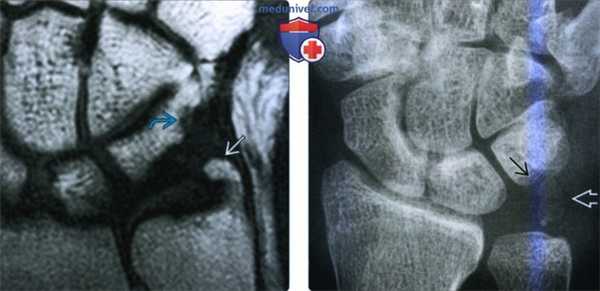

(Слева) На фронтальной МРТ Т1ВИ определяется склеротическая неровность проксимальной поверхности трехгранной кости. Длинный и крючковидный шиловидный отросток локтевой кости врезается в тыльную медиальную поверхность трехгранной кости, повреждая хрящ, что приводит к субхондральному склерозу.

(Справа) На заднепередней рентгенограмме определяется незначительный импичмент проксимальной поверхности трехгранной кости, покрытой выраженным кортикальным слоем, округленным основанием шиловидного отростка локтевой кости с несросшимся переломом. Постоянная боль может быть обусловлена непосредственным сдавливанием кости или сопутствующим разрывом треугольного фиброзно-хрящевого комплекса.